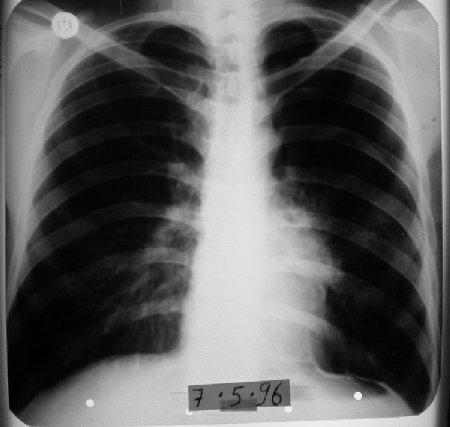

31 yaşında erkek hasta • 7 ayda tam iyileşme

1995 yılında küçük hücreli anaplastik karsinom teşhisi konulan 31 yaşındaki erkek hasta, kemoterapiyi reddederek immünomodülatör tedavi ile 7 ayda tam iyileşme sağladı. Şiddetli ağrıları sadece 12 günde kayboldu ve röntgende tümör tamamen ortadan kalktı.

1996 Mayıs - Tam İyileşme

Röntgende tümör tamamen kayboldu

1996 Mayıs (7. Ay)

Röntgen tümörün tamamen kaybolduğunu gösterdi.

Radyolojik Kanıt: Röntgende tümör tamamen kayboldu

• Radyolojik tam yanıt 7 ayda elde edildi

7 aylık süreçte tam iyileşme

Küçük hücreli anaplastik karsinomun tamamen ortadan kalkması